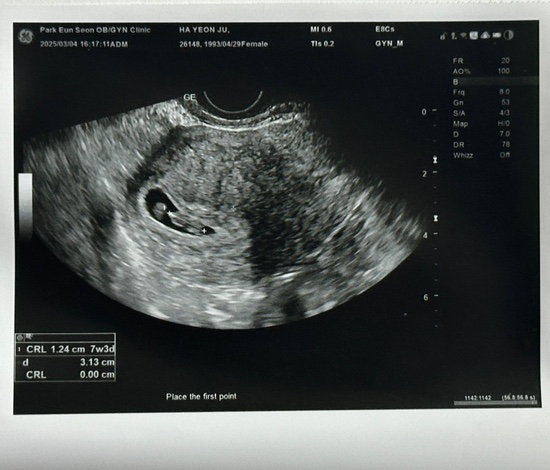

#2 배란일 10일차~14일 임테기 역전까지의 기록, 4주 아기집확인

배란일10일차부터 14일차까지의 기록 배란 +10 전날 밤부터 몸이 너무 안 좋고 새벽에 잠 깰 정도로 배가 ...